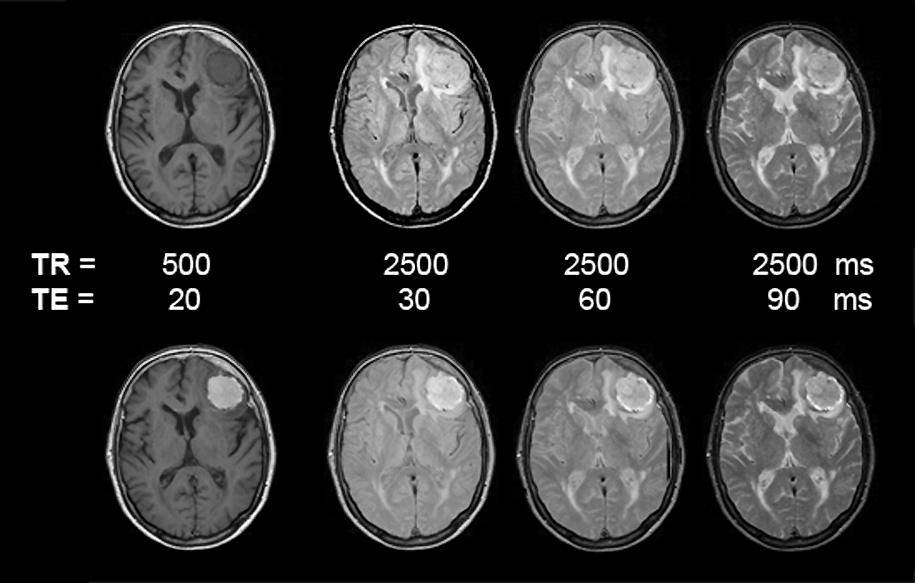

Figuras 13-09:

Pa­tient with a meningioma. Multiple SE sequence before (top row) and after (bottom row) intravenous application of a gadolinium contrast agent. The images to the left are heavily T1-weighted, then ρ-weighted, and to the right increasingly T2-weighted.

Simulation software: MR Image Expert®

Animation of contrast-enhanced images; pa­tient with a meningioma; TR = 800 ms; TE bet­ween 20 and 120 ms (= T1-weighted to T2- in­flu­en­ced). The contrast-agent enhancement of the tumor slowly disappears (cf. Figure 13-08 a; plain images and enhanced images).

The patient of the figure above has a huge meningioma in the left frontal lobe. It is easily visible on the non-enhanced images, mostly because of its mass effect and the bright surrounding edema on T2-weighted images. Yet, this case is a good example of the enhancement pattern of gadolinium contrast agents. This kind of tumor enhances brightly on T1-weighted images; there is still enhancement on ρ-weighted images. T2-weighted images, however, show the same contrast pattern before and after injection of the agent. If the meningioma or similar enhancing lesions are very small and no indirect signs of lesions can be found, only contrast enhancement will reveal the pathology (see also Figure 13-04 and Figure 13-08).